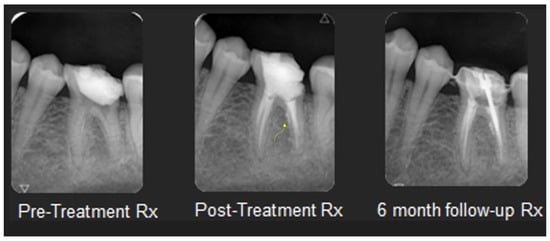

2.5. Non-Divergent Open Apex